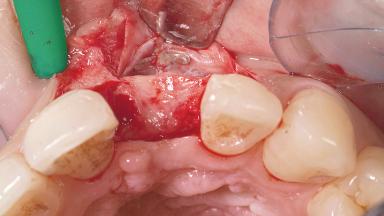

A 30-year-old female patient had lost tooth 21 and was referred to our clinic for consultation and treatment. Due to advanced apical infection, tooth 21 had been extracted two months earlier at another clinic and an acrylic-resin tooth had been bonded to the adjacent teeth. The patient desired implant treatment to avoid any damage to the adjacent natural teeth. While the patient had no history of any systemic disorder, she was a heavy smoker and exhibited medium to advanced periodontitis in the entire jaw. After the initial treatment to achieve a pocket probing depth of less than 4 mm and no bleeding on probing, a decrease in the height of the papillae mesial and distal to the extraction site and overall gingival recession were observed.

Bone Augmentation Horizontal|Staged

Augmentation Materials Autogenous chips|Membrane

Soft Tissue Grafting Simultaneous